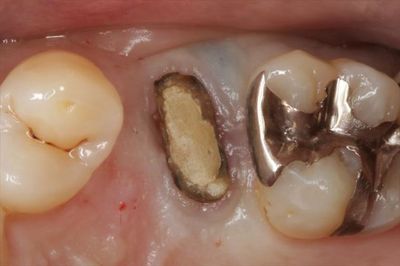

実際の左上第二小臼歯の状態です。

慎重に一旦抜歯しました。

黒っぽく透けて見えている部分の内部に金属(ヤスリのカケラ)が存在しています。